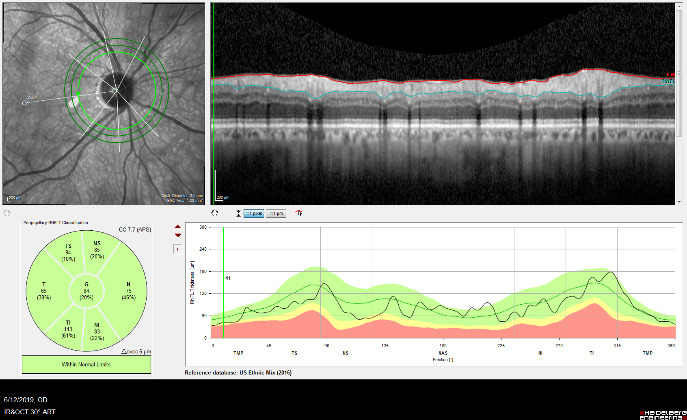

Optical Coherence Tomography (OCT) is an advanced imaging technology that has revolutionized the diagnosis and management of eye disease, especially glaucoma and retinal disease. OCT is a non-invasive method of imaging structures in the eye at an extremely high, microscopic resolution.

OCT uses infrared light to create cross-sectional, three-dimensional images of the tissues in the eye. As is the case for laser treatments, the eye is particularly amenable to imaging with OCT because the eye is optically transparent.

OCT Imaging of the Nerve Fiber Layer

OCT is used in glaucoma to image the optic nerve and the nerve fiber layer in order to determine if there is damage from increased eye pressure. Because the resolution of OCT is so high, it can detect fine changes to the shape of optic nerve. Thinning of the nerve fiber layer is a sign that glaucoma is worsening and that the eye pressure is too high.

OCT Imaging of a Normal Optic Nerve

An example of an optic nerve with glaucoma damage imaged with both fundus photography and OCT and compared to the visual field in order to demonstrate the strucure-function relationship.

The lower half of the optc nerve has early damage, and this correlates with the small superior scotoma seen on the visual field test.